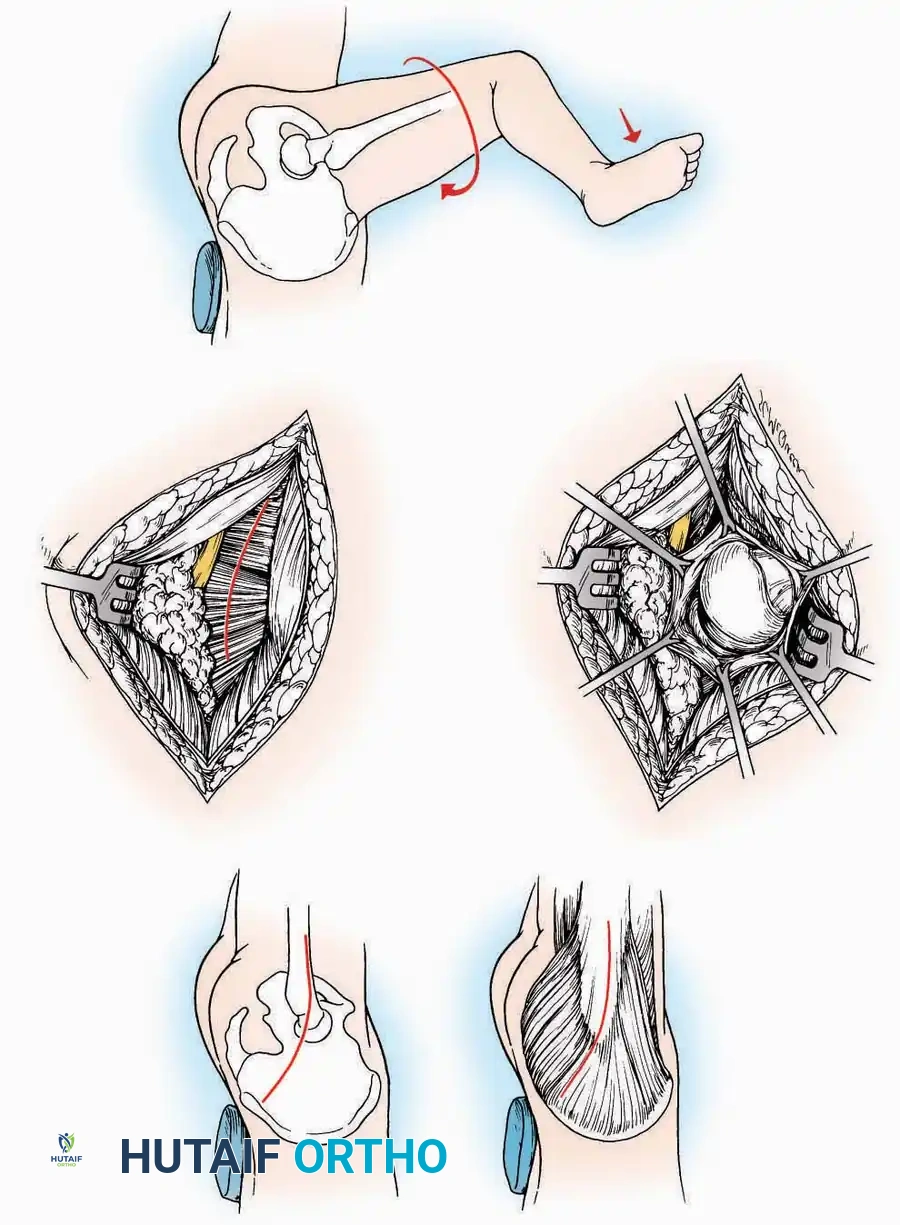

Approaches to the Metatarsophalangeal (MTP) Joint of the Great Toe

The first MTP joint is the epicenter of forefoot reconstructive surgery. Exposure can be achieved via medial or dorsomedial trajectories.

Medial Approach

Indications: Hallux valgus correction (bunionectomy), first MTP arthrodesis, or cheilectomy.

Surgical Technique:

* Incision: Make a curved incision 5 cm long on the medial aspect of the joint. Begin just proximal to the IP joint, curve it over the dorsum of the MTP joint (medial to the extensor hallucis longus [EHL] tendon), and terminate on the medial aspect of the first metatarsal 2.5 cm proximal to the joint.

* Superficial Dissection: As the deep fascia is incised, identify and laterally retract the medial branch of the first dorsal metatarsal artery and the medial branch of the dorsomedial nerve (a terminal branch of the superficial peroneal nerve).

* Deep Dissection: Dissect the fascia from the dorsum down to the bursa overlying the medial eminence of the metatarsal head.

* Capsulotomy: Make a curved incision through the bursa and joint capsule. Begin dorsomedially, continue proximally dorsal to the metatarsal head, sweep plantarward, and end distally on the medioplantar aspect of the joint. This creates an elliptical, racquet-shaped flap attached at the base of the proximal phalanx.

⚠️ Surgical Pitfall

While distal reflection of this racquet flap provides ample exposure of the first MTP joint, the extensive subfascial undermining required can compromise the vascularity of the skin flap, leading to delayed healing or necrosis. Consequently, the dorsomedial approach is often preferred in modern practice.

Dorsomedial Approach

Indications: Preferred approach for primary and revision first MTP arthroplasty, arthrodesis, and complex bunion corrections due to superior angiosome preservation.

Surgical Technique:

* Incision: Begin just proximal to the IP joint and extend proximally for 5 cm, running parallel and strictly medial to the EHL tendon.

* Exposure: Divide the superficial fascia. Identify and retract the EHL tendon laterally.

* Capsulotomy: The capsule can be incised longitudinally in the exact plane of the skin incision, allowing for subperiosteal elevation of the capsule medially and laterally, preserving the vascular supply to the medial skin flap.